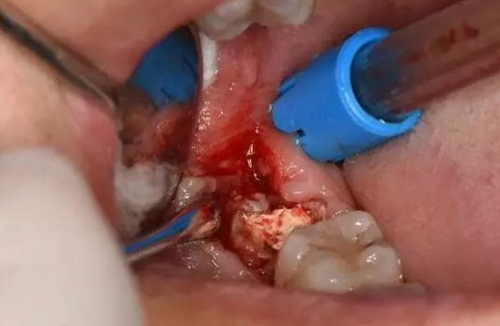

圖8.近中放置牙挺、挺松48